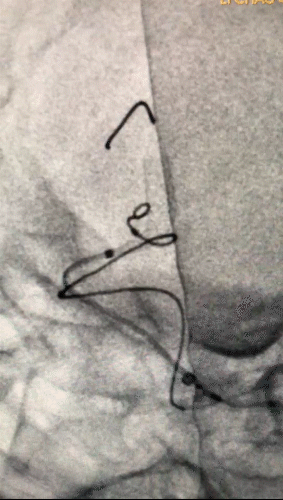

3.1)

回撤到平直段,半释放pipeline

3.2)

Navien继续上高,推支架,确保瘤颈处支架的贴壁